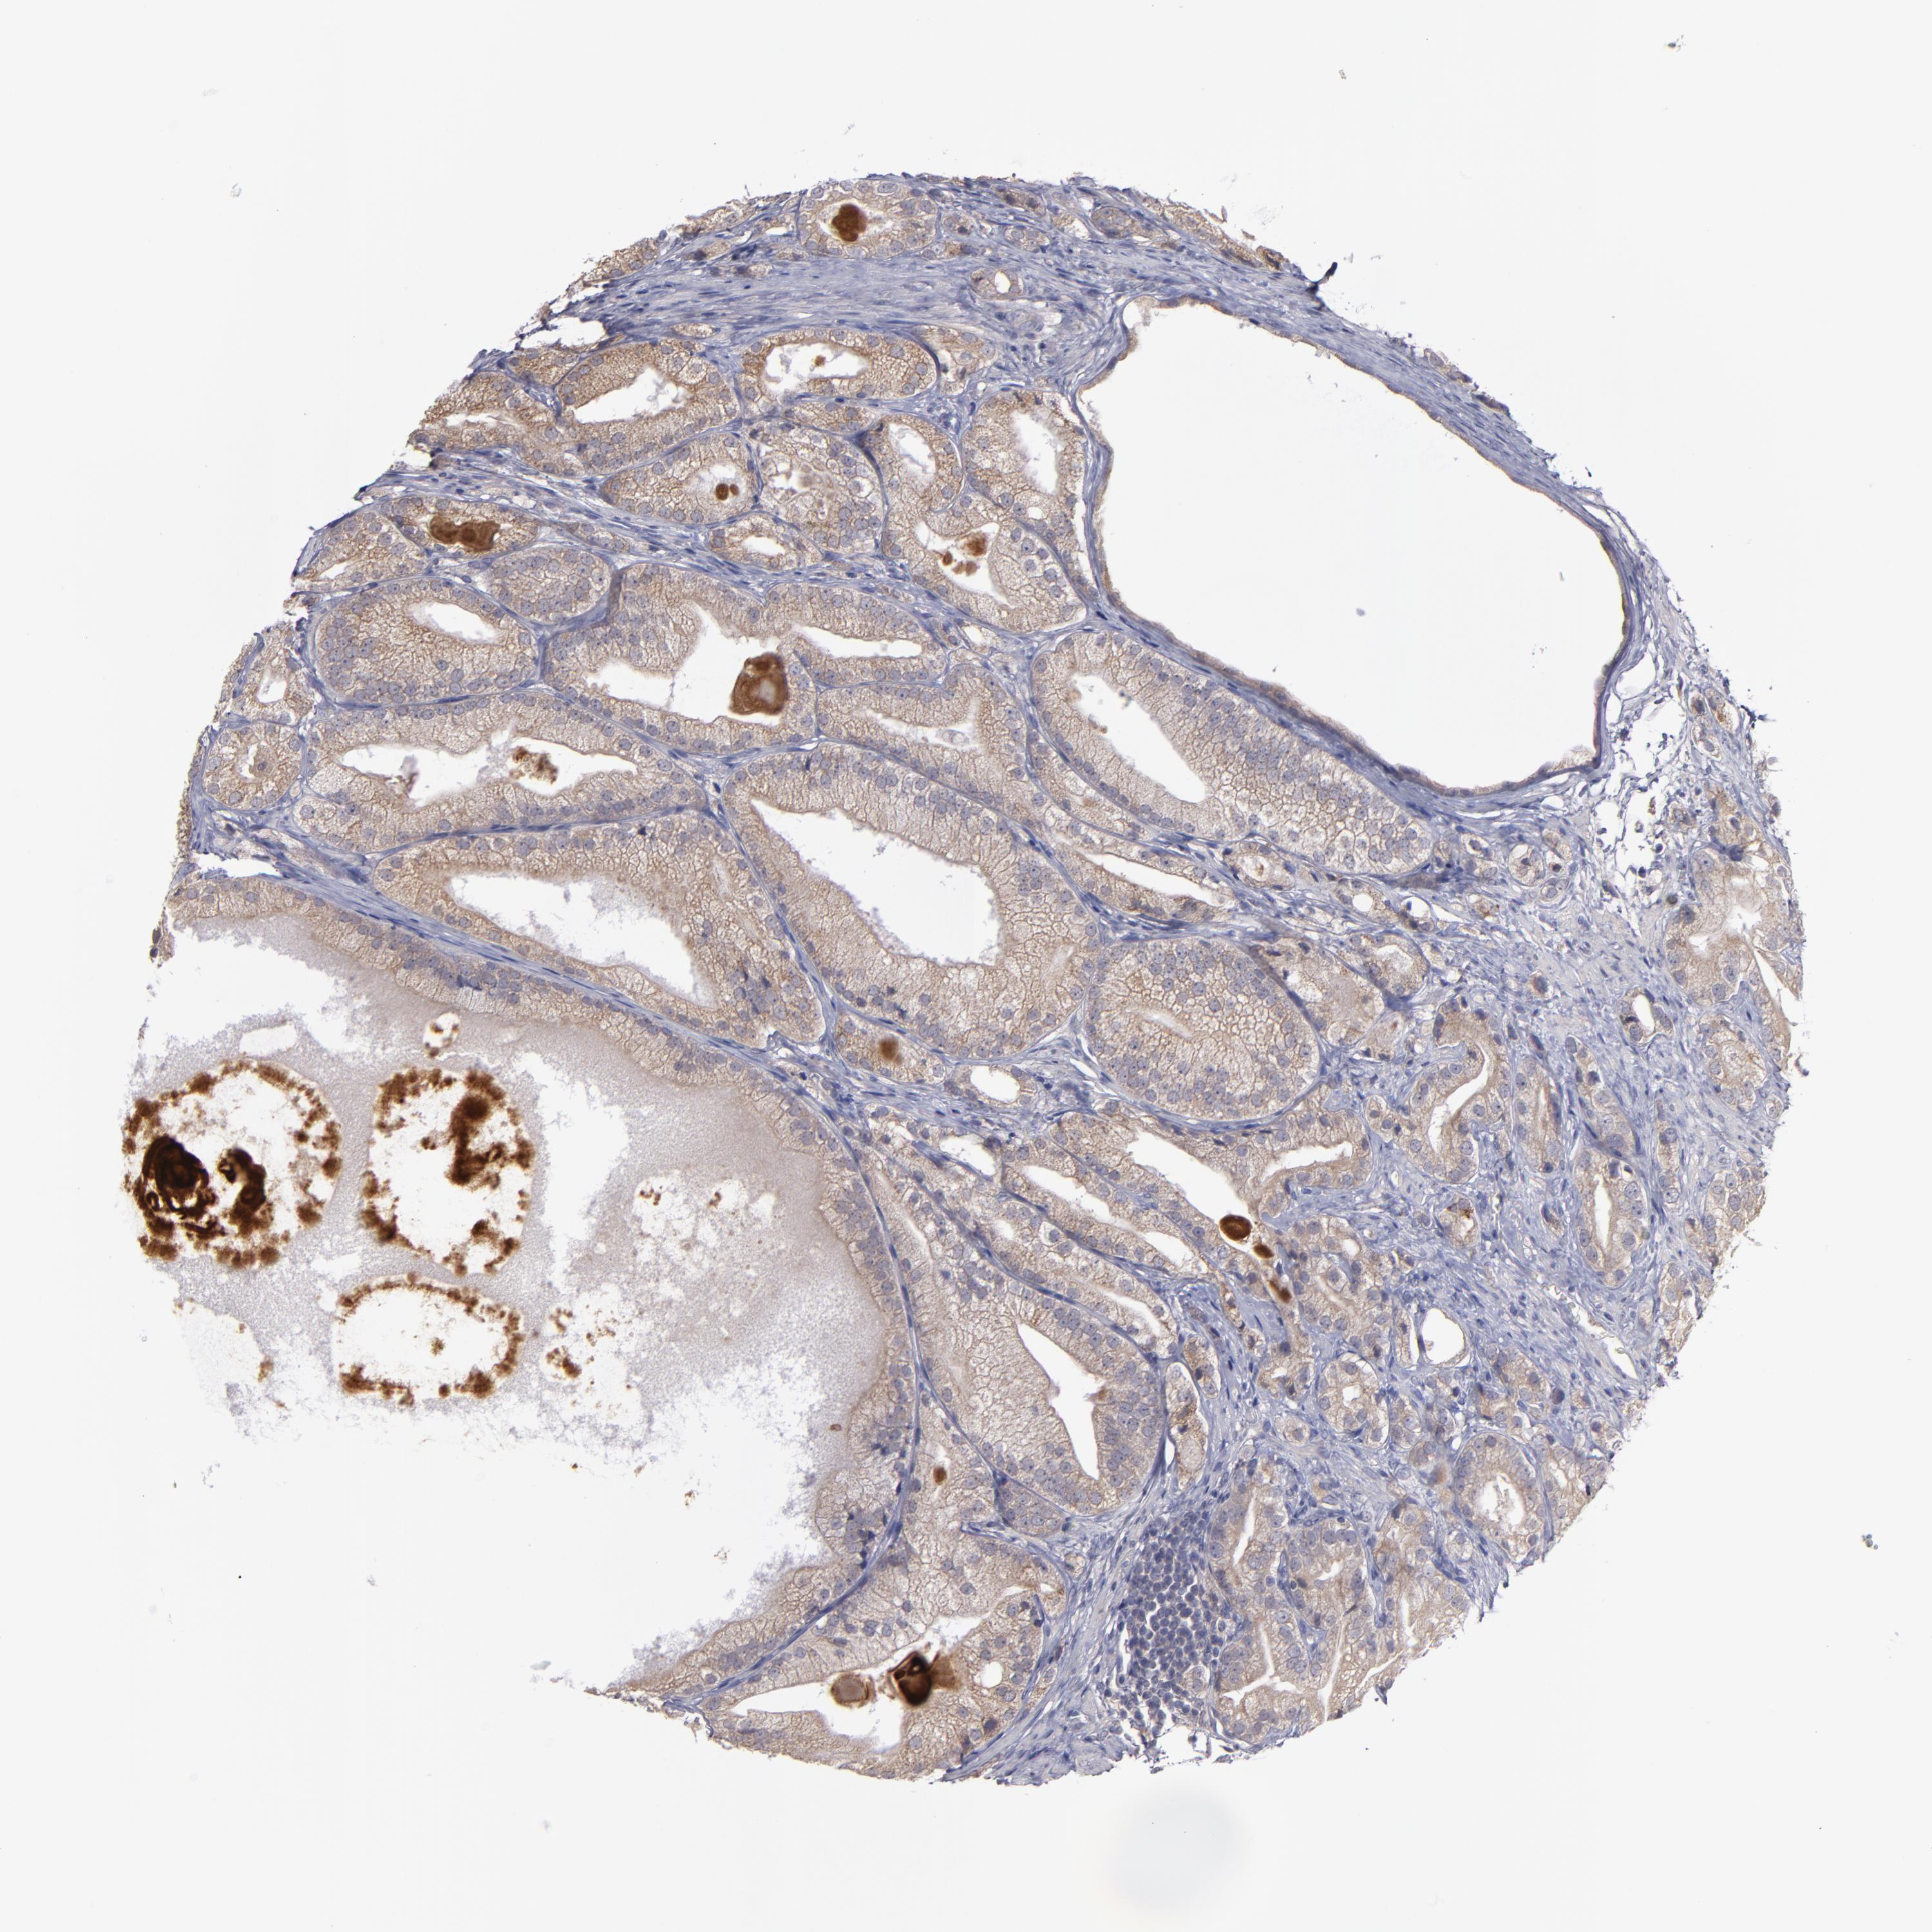

PROSTATE CANCER - Protein expressioni

A mouse-over function shows sample information and annotation data. Click on an image to view it in a full screen mode. Samples can be filtered based on level of antibody staining by selecting one or several of the following categories: high, medium, low and not detected. The assay and annotation is described here.

Note that samples used for immunohistochemistry by the Human Protein Atlas do not correspond to samples in the TCGA dataset.

Antibody stainingi

Antibody staining in the annotated cell types in the current human tissue is reported as not detected, low, medium, or high, based on conventional immunohistochemistry profiling in selected tissues. This score is based on the combination of the staining intensity and fraction of stained cells.

Each image is clickable and will lead to virtual microscopy that enables deeper exploration of all samples and also displays staining intensity scores, fraction scores and subcellular localization as well as patient and tissue information for each sample.

Antibody HPA068864

Antibody CAB002593

Staining

High

Medium

Low

Not detected

Intensity

Strong

Moderate

Weak

Negative

Quantity

>75%

75%-25%

<25%

None

Location

Nuclear

Cytoplasmic/membranous

Cytoplasmic/membranous,nuclear

Adenocarcinoma, High grade

Adenocarcinoma, Low grade

Adenocarcinoma, Medium grade